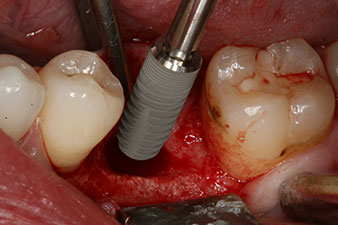

No obstante, seis semanas después de la extracción, tras la disección del colgajo mucoperióstico, se observó una osificación incompleta en el área del antiguo alvéolo mesial.

Tras la extirpación minuciosa del tejido de granulación, se incorporó el implante tal como se había planificado (blueSky, bredent).

El torque en el momento de la carga mecánica fue de 43 Ncm. Asimismo, después de atornillar un poste de medición especial adaptado al sistema de implante (SmartPeg), el valor ISQ se determinó con la sonda del módulo Osstell ISQ de W&H.

Este módulo Osstell ISQ que se encuentra disponible como accesorio para la unidad Implantmed de W&H y se acopla al motor de implantes (véase figura 11). El valor ISQ adimensional fue de 64 justo en el momento de la inserción en la dirección bucovestibular y de 68 en la dirección mesiodistal (valor máximo = 100).

Este habría permitido una cicatrización abierta o incluso un tratamiento inmediato. Sin embargo, como no se disponía de suficiente hueso en la parte crestal del implante, el área se aumentó con las virutas óseas recopiladas durante la preparación del lecho del implante y se suturó para que no penetrara saliva.